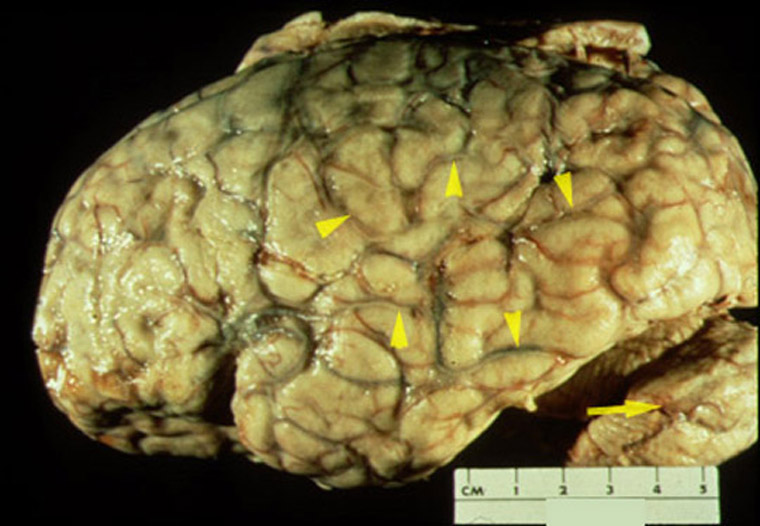

- Bacterial meningitis: the autopsy specimen

consists of the brain without the dura mater. The sulci contain pus (arrows) which discolors the veins yellow. The leptomeninges covering the cerebral hemisphere is cloudy because of the acute

inflammation.